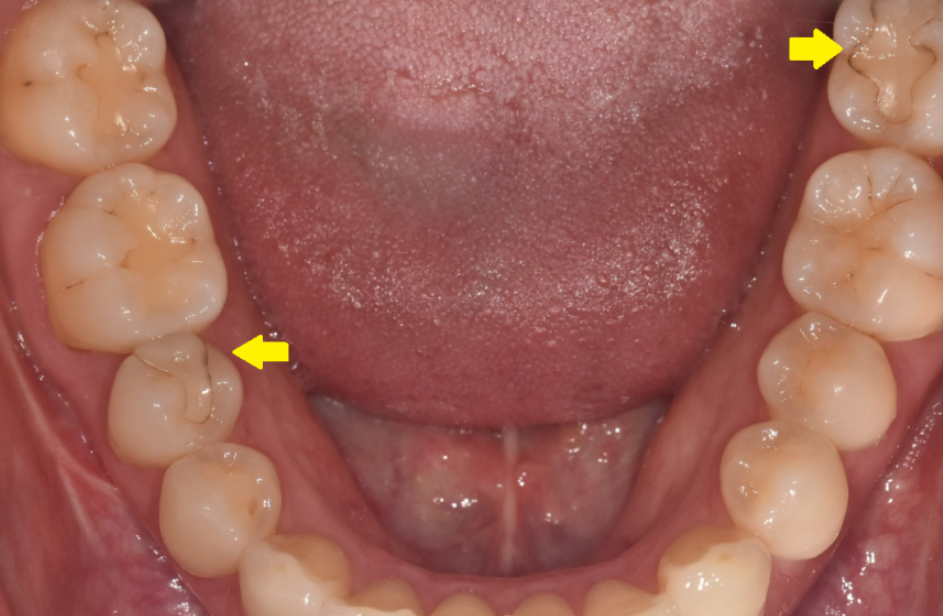

1. 심미성이 뛰어납니다: 치아 색상과 매우 유사하여 치료 부위가 눈에 띄지 않습니다. 특히 아래쪽 어금니를 치료할 때 만족도가 높습니다.

하이브리드 인레이 보철물의 미세한 변색 및 자연 치아 마모도 시각 자료